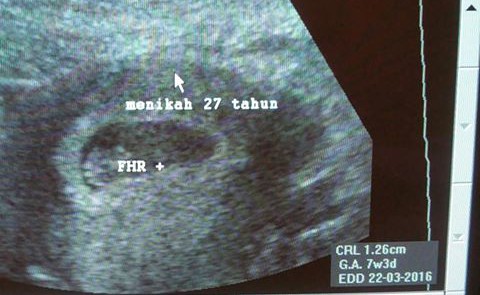

Salah seorang dokter kandungan, Suryo Bawono, menuliskan pengalaman di akun Facebooknya tentang wanita yang baru hamil anak pertama setelah 27 tahun menikah. Penantian yang sungguh luar biasa, 27 tahun tentunya bukan waktu yang sebentar untuk mengharapkan datangnya seorang keturunan.

"Saya ikut berdebar waktu melakukan pemeriksaan. Bagaimana tidak, denyut jantungnya lama dicari tidak ketemu, sedangkan kehamilan sudah berjalan 7 minggu," tulis Suryo di Facebook seperti dikutip brilio.net, Minggu (9/8).

"Alhamdulillah akhirnya terdengar detak janinnya, saya ikut menarik napas panjang, lega sekali rasanya. Dalam hati saya berdoa agar pasien tersebut tersenyum bahagia nanti saat buah hatinya bisa lahir dengan sehat dan selamat," lanjutnya.

Menurut Suryo, ibu janin tersebut sudah berusia 40 tahun lebih. Memang ada kekhawatiran bagi ibu yang hamil di usia lebih dari 40 tahun. Namun tidak menjadi halangan seorang ibu untuk melahirkan, apalagi ini merupakan penantian terlama. Semoga ibu dan calon bayinya sehat selalu.